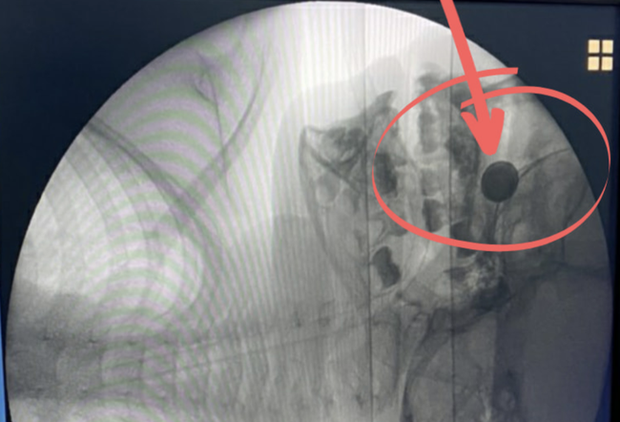

Theo bệnh sử, ngày 4/7 bé H. (4 tuổi, ngụ tỉnh Đồng Nai) chơi giỡn rồi tự nhét cục pin hình nút áo vào hốc mũi khiến máu chảy nhiều. Nghiêm trọng hơn, axit của pin đã nhanh chóng phá hủy hốc mũi và thành mũi.

Mãi đến 3 ngày sau, gia đình mới đưa bé đến cấp cứu tại Bệnh Viện (BV) Nhi Đồng 2 (TP.HCM).

Tại đây, các bác sĩ đã thăm khám, chỉ định chụp X-quang cho bé H. Phát hiện dị vật hốc mũi, bác sĩ đã tiến hành lấy dị vật bằng phương pháp gây tê. Tuy nhiên cách này không thành công vì dị vật nằm rất sâu trong hốc mũi, mũi chảy máu nhiều và axit của pin đang gây phá hủy hốc mũi và thành mũi.

Sau hội chẩn, bác sĩ Nguyễn Tường Thi, khoa Liên chuyên khoa quyết định chuyển sang lấy dị vật bằng phương pháp gây mê.

Sau 2 giờ phẫu thuật bằng phương pháp nội soi cấu trúc dẫn đường, dị vật đã được lấy ra thành công. Can thiệp này giúp bé khỏe lại, được cấp toa cho về. Dự kiến bệnh nhi sẽ tái khám theo dõi định kỳ do việc hốc mũi và thành mũi bị phá hủy bởi axit sẽ ảnh hưởng đến di chứng về sau.